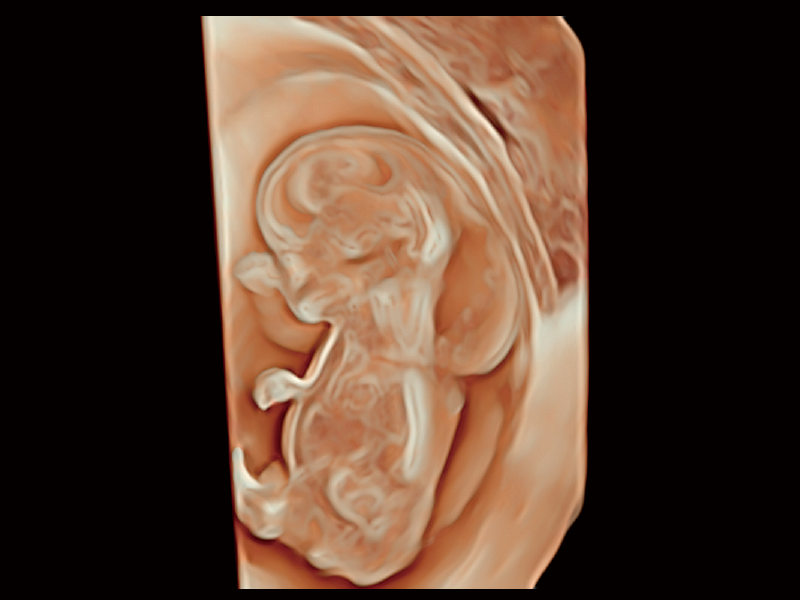

梦溪®P80以“关爱女性”为基石,提供全方位的解决方案,量身定制以满足女性的健康需求,涵盖妇科、生殖健康检查、产前筛查及产后康复等领域。